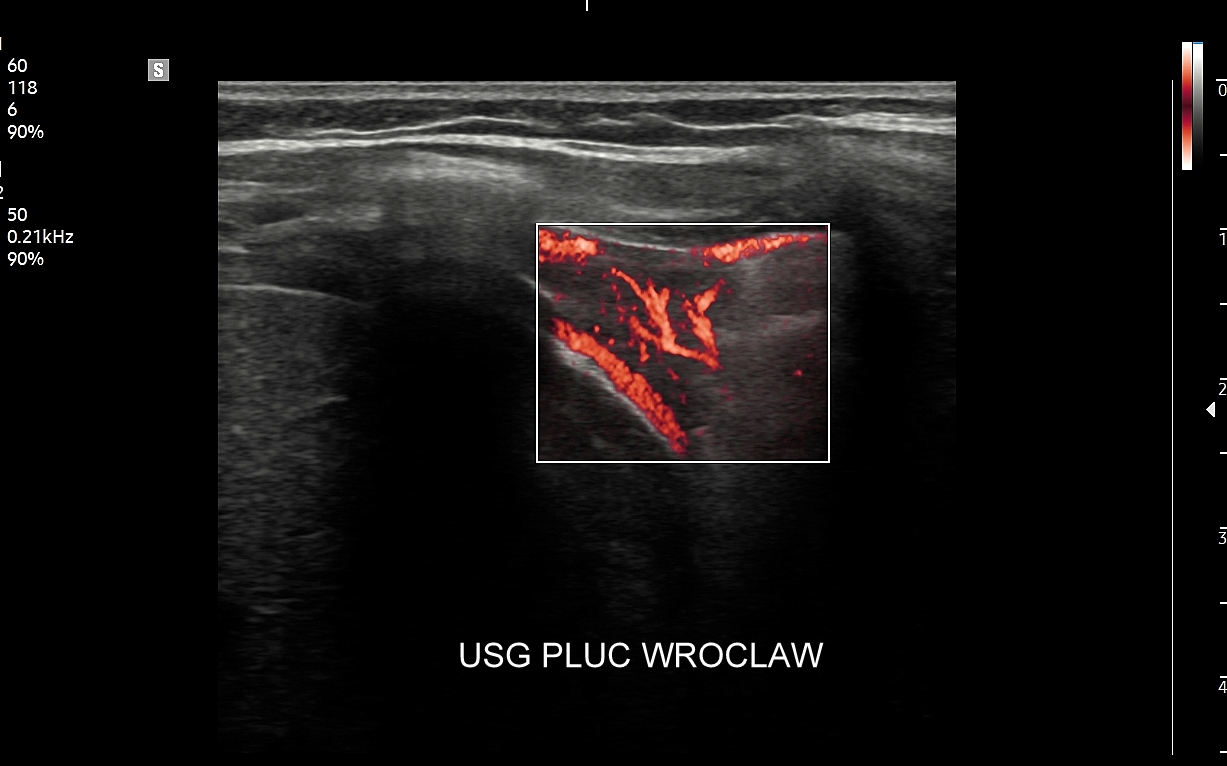

Dr Tomasz Szczepański zajmuje się kompleksową opieką medyczną nad swoimi Pacjentami. W ramach Interdyscyplinarnej Pracowni USG Wrocław wykonuje szereg uzupełniających się badań, zarówno klasycznych, jak USG jamy brzusznej, USG tarczycy, USG piersi, pełen zakres diagnostyki USG Doppler, jak i wysokospecjalistycznych, w tym badania multiparametryczne (MPUS), badania USG z kontrastem (CEUS), ocena przetok dializacyjnych, badania USG Doppler przepływów nerkowych, czy badania USG twarzy

USG płuc | Można powiedzieć, że Pan Doktor uratował życie mojego Taty. Wykrył w USG zakrzep w płucu, którego nikt wcześniej nie zauważył. Gdyby nie to mój Tata mógłby się udusić w trakcie ataku. Dziękujemy serdecznie. Dominika K. | Polska